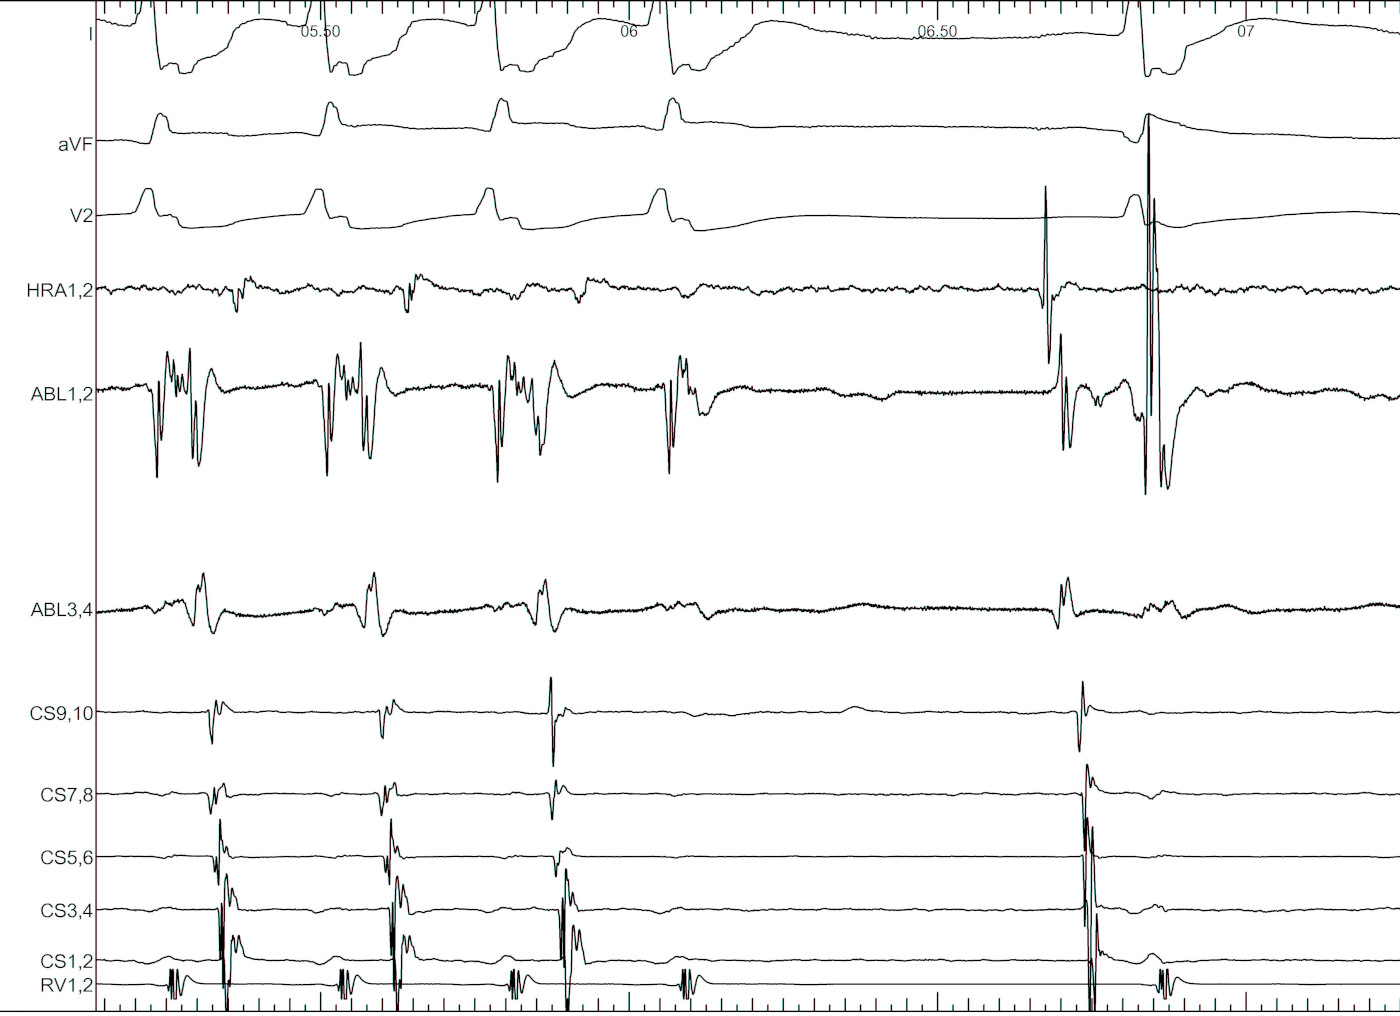

Unipolar EGM

unipolar.jpg

good_signal_llap_antegrade.png